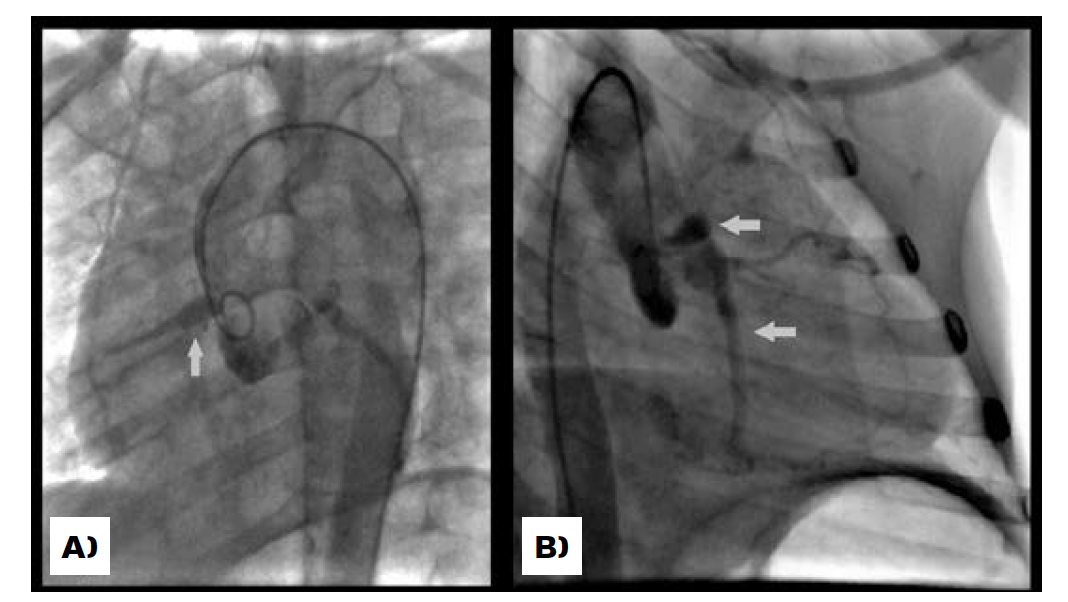

Case 3

A 6-year-old boy with refractory Kawasaki disease required 2 cycles of intravenous immunoglobulin, antiplatelet and systemic corticosteroid therapy, and showed on day 11 significant ectasia of both coronary arteries: the right coronary artery measured 3.8 mm (Z-score of +4) and left coronary artery 4.1 mm (Z-score of +3.5).

He was discharged home on day 13 on antiplatelet therapy, but was readmitted twelve days later with fever. The echocardiogram showed worsening of the coronary artery ectasia (Figure 3): the right coronary artery measured 6 mm (Z-score of +9.7), the circumflex artery 3.8 mm (Z-score of +2.7), and the left anterior descending artery 7 mm (Z-score of +13). He was started on cyclosporin, systemic corticosteroids, as well as anticoagulant and antiplatelet therapy. Fever resolved promptly but his inflammatory markers took eight days to normalize.

During follow-up the coronary ectasia did not regress and a CT angiogram was carried out, showing, in addition, the presence of giant coronary artery with no significant stenotic lesions. Further investigation showed dilatation of the proximal superior mesenteric artery and small fusiform dilatation of the anterior communicating artery (Figure 4). A treadmill stress test showed no signs of ischemia.